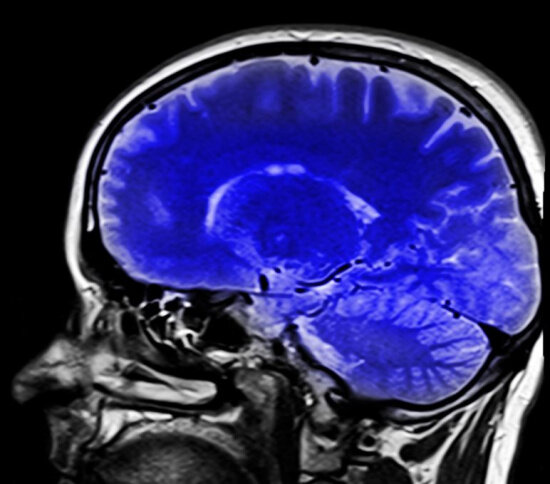

Ученые раскрыли опасность бытовых веществ для мозга, сделали это сотрудники Медицинской школы Университета Кейс Вестерн Резерв в США. Исследования опубликовали в журнале Nature Neuroscience.

Так, химикаты могут быть связаны с неврологическими заболеваниями, такими как рассеянный склероз и расстройства аутистического спектра. Содержащиеся в них вещества воздействуют на олигодендроциты мозга, специализированный тип клеток, который создает защитную изоляцию вокруг нервных клеток.

Одни из таких веществ вызывают гибель олигодендроцитов, а другие предотвращают их созревание. Потеря олигодендроцитов лежит в основе многих неврологических заболеваний.